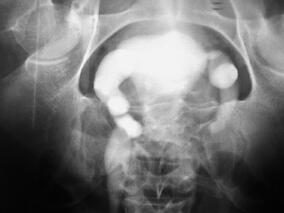

排尿困难伴双肾积水6年余 缘何诊治歧义?

1小时条评论【病例资料】 患者男性,27岁。 主诉:排尿困难伴双肾积水6年余。 现病史:6年前,患者因排尿困难伴左肾绞痛,于当地医院就诊,诊为:双肾输尿管积水;膀胱憩室;膀胱颈部梗阻。行膀胱憩室切除+左输尿管再植+膀胱颈部楔形切除术治疗,术后病理提示:左输尿管开口...